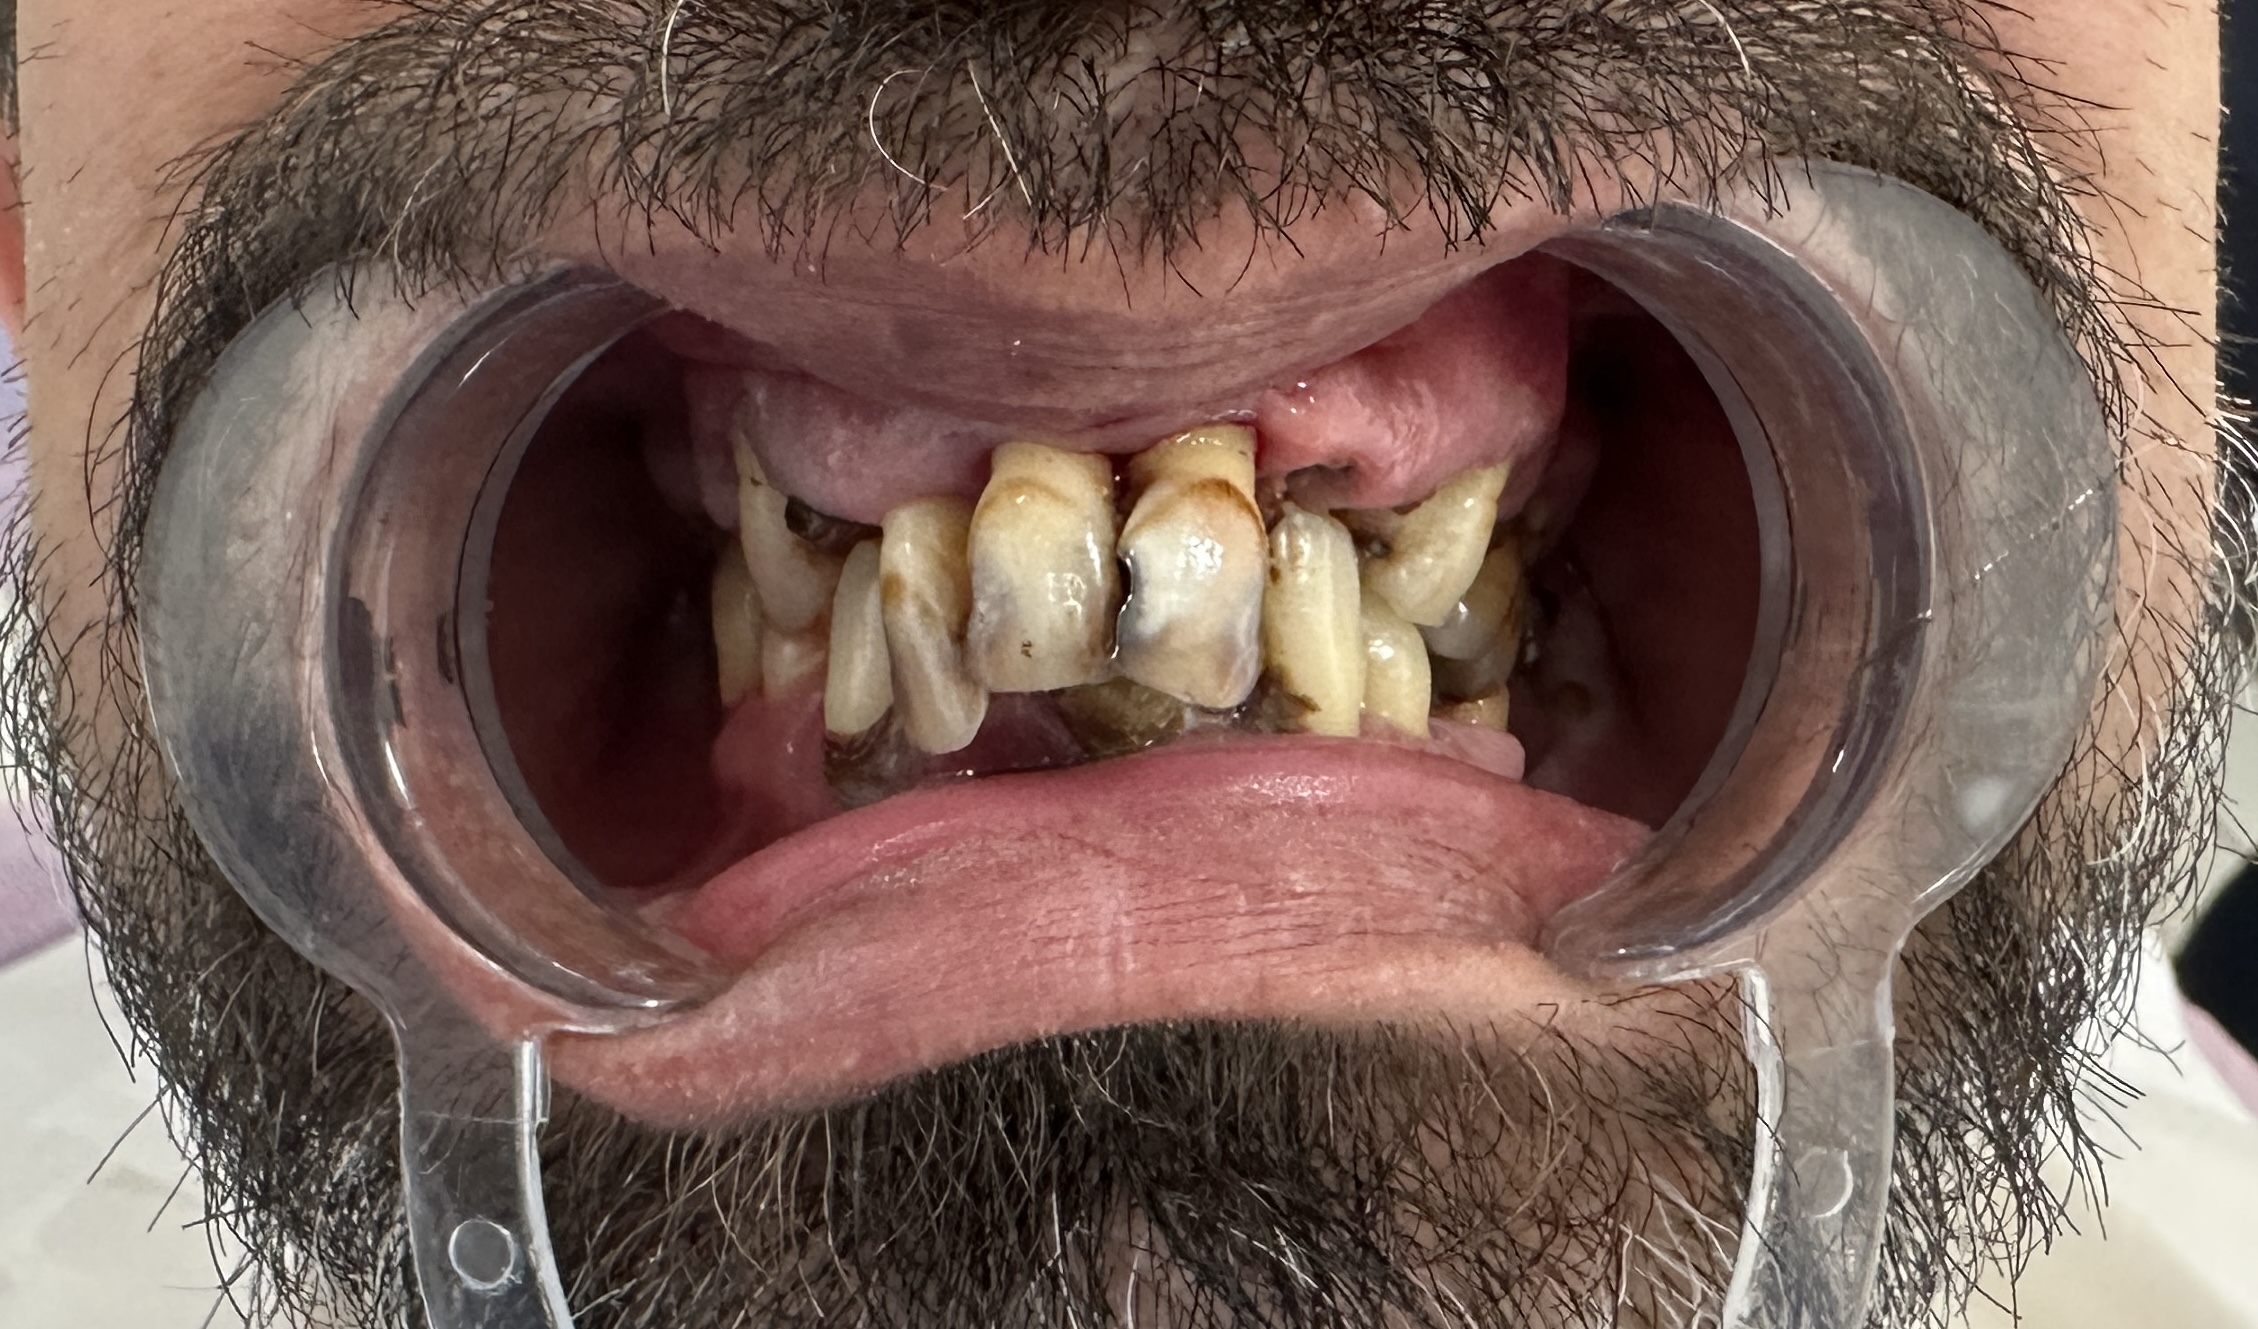

Öncesi Sonrası

Öncesi

Sonrası